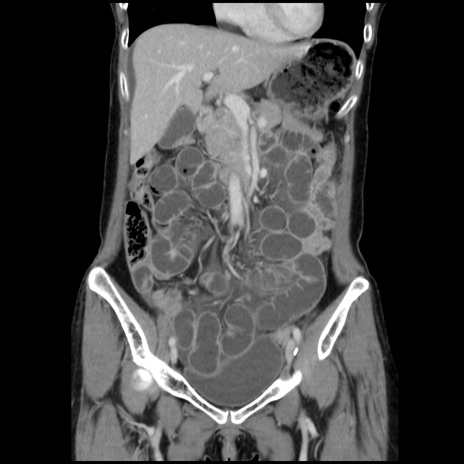

症例32(冠状断像)

【症例】40歳代 女性

【主訴】上腹部痛、嘔気・嘔吐

【現病歴】約9時間前頃から急に上腹部痛、嘔気、嘔吐が出現。改善しないため救急要請。

【既往歴】子宮頚癌(広汎子宮全摘術、放射線療法)、腸閉塞

【身体所見】腹部:平坦、軟、腸雑音亢進、上腹部を中心に腹部全体に圧痛あり。

【データ】WBC 8400、CRP 0.03